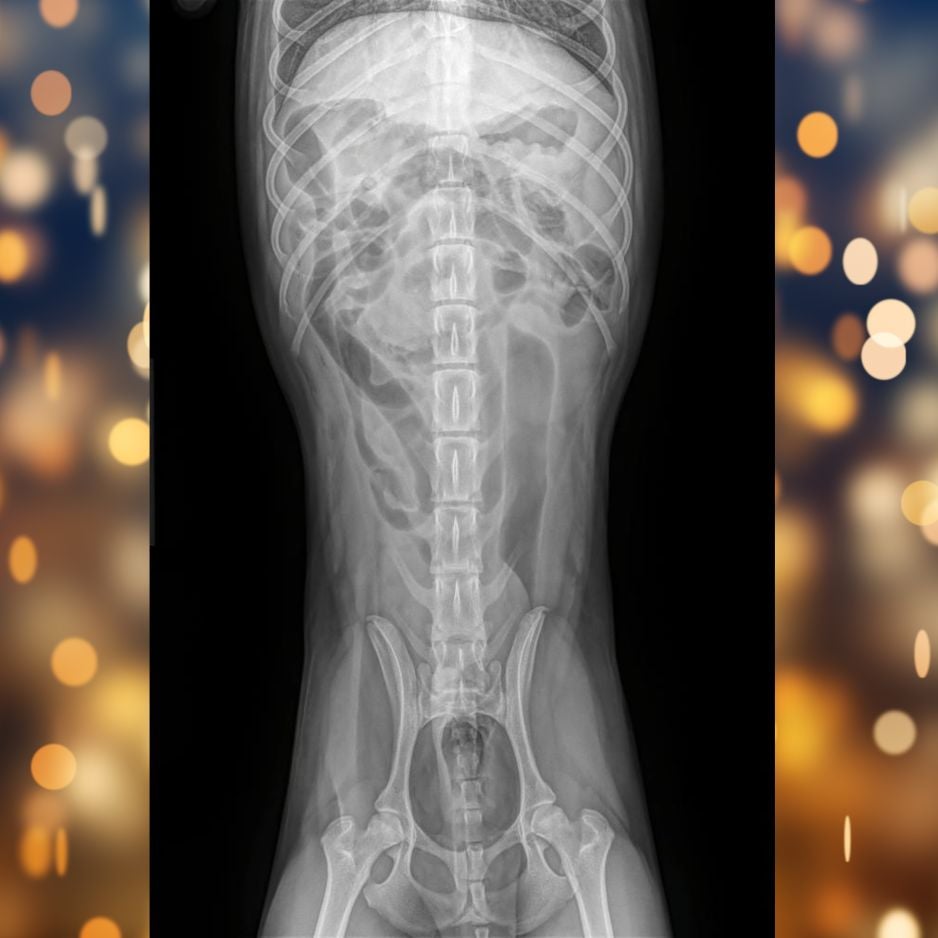

X-rays confirmed our suspicion — fabric material was visible in Tito’s small intestine, causing a blockage in his gastrointestinal tract. This meant food and fluids couldn’t move through normally, leading to pain, dehydration, and vomiting.

Tito X-rays